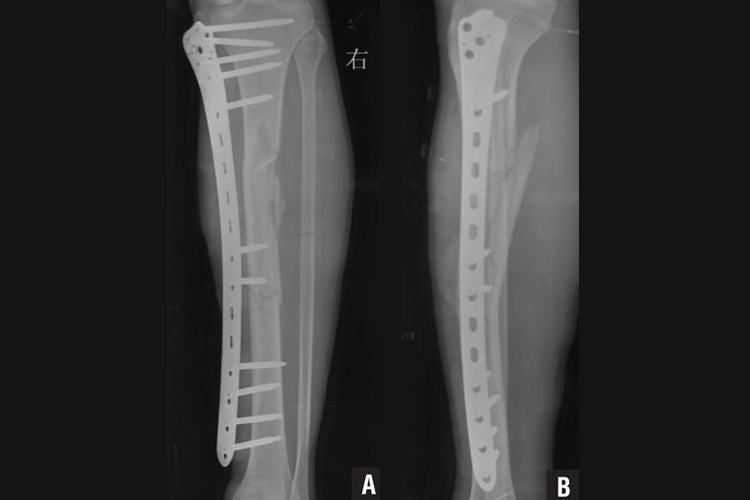

胫骨骨折

胫骨骨折可采取钢板钢钉内固定,于开放复位后,用钢钉、钢板在骨折部位固定,用以维持骨折对位。由于胫骨前内侧皮肤及皮下组织较薄,因此钢板可放在胫骨外侧胫前肌的深面。